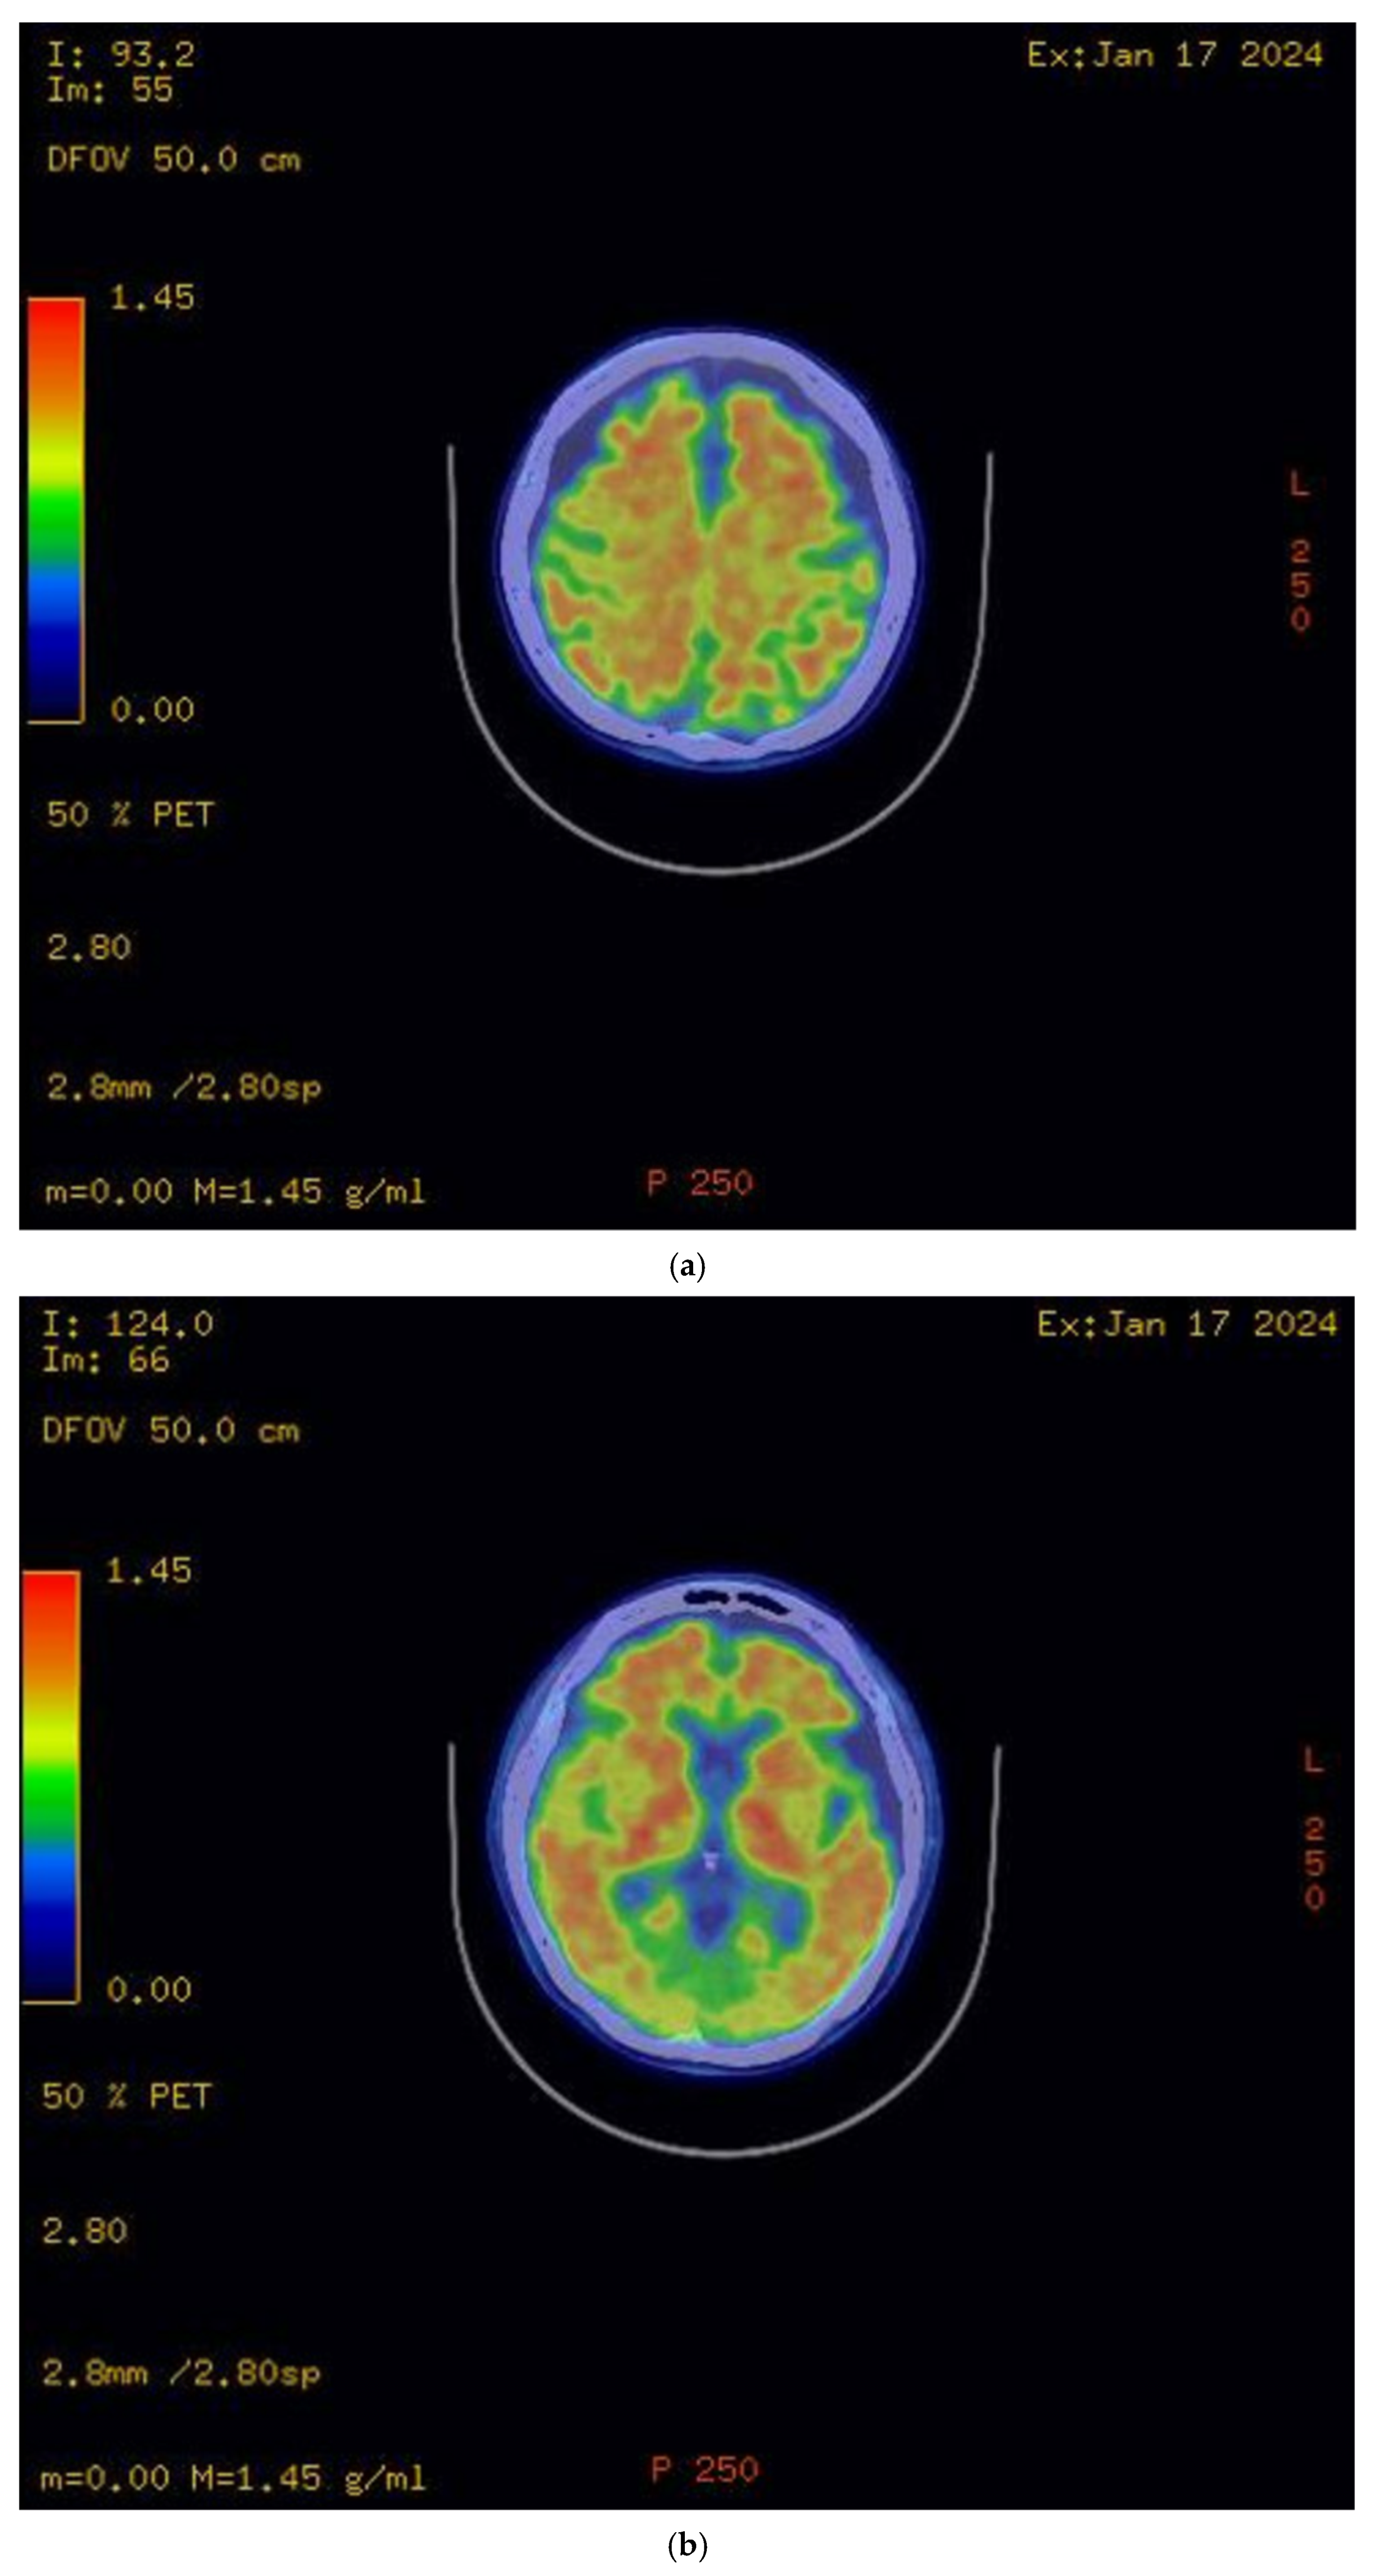

The initial brain MRI conducted in March 2023 demonstrated global cerebral involution with equivocal frontoparietal predilection and relative medical temporal lobe sparing. Global cortical atrophy (GCA) grade 1–2 was reported, showing mild to moderate brain atrophy with a reduced gyri volume, increased sulci and moderate ventricular dilatation [5]. There was evidence of progressive neurodegenerative changes in the brain MRI findings one year later; the second brain MRI in April 2024 showed predominant bilateral frontal and parietal volume loss, sparing the occipital and temporal lobes. A medial temporal lobe atrophy score (MTA) of grade 1 was reported (Figure 2). Amyloid positron emission tomography (PET) (Figure 3) confirmed the presence of amyloids, a hallmark of Alzheimer’s disease. While a lumbar puncture to measure cerebrospinal fluid (CSF) biomarkers (Aβ1-42 and tau) was offered, the family declined due to the invasive nature of the procedure.

Figure 2.

(a–c): MRI FLAIR sequence (from left to right): (a) significant symmetrical gyral thinning in frontal and parietal lobes; (b) significant symmetrical gyral thinning in frontal lobes, mostly sparing the occipital lobes; (c) reasonably preserved hippocampal volumes bilaterally.